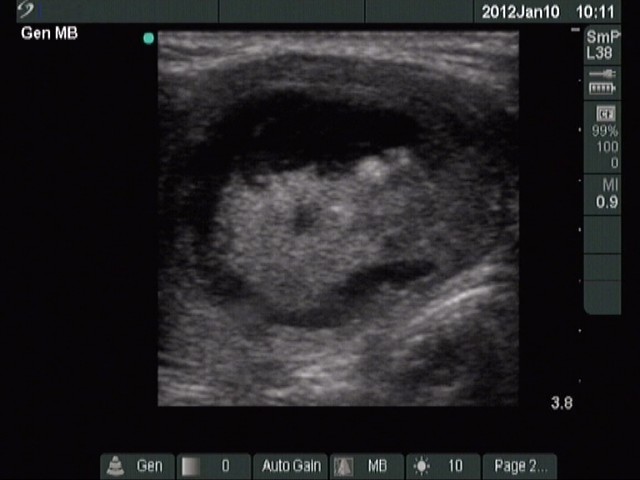

Ethanol sclerotherapy: thyroid cysts - Case 1

Second session of sclerotherapy (ultrasonographic picture 1)

Isthmic part of the right lobe, horizontal scan. There is no change in size or pattern of the nodule compared with previous examination.